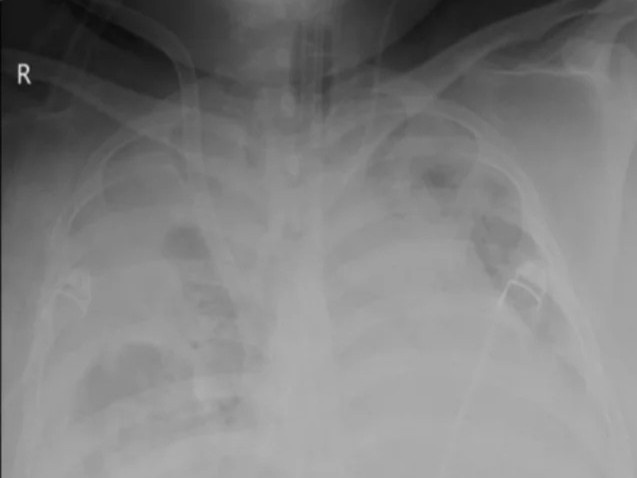

Hình ảnh lá phổi của bệnh nhân trên X-quang bị mờ do tổn thương nặng. Ảnh: BVCC.

Trên phim X-quang, hình ảnh phổi bị đông đặc đến 80% thể tích. Lúc này, sự sống của bệnh nhân 28 tuổi phải hoàn toàn phụ thuộc vào ECMO.